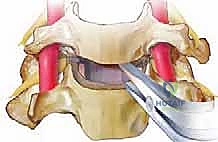

الخطوة 4: استئصال القرص الغضروفي (Discectomy)

باستخدام أدوات ميكروسكوبية دقيقة، يتم تفريغ وإزالة القرص الغضروفي التالف بالكامل. يتم كشط الغضروف حتى الوصول إلى السطح العظمي للفقرتين العلوية والسفلية.

الخطوة 5: تخفيف الضغط العصبي (Decompression)

هذه هي المرحلة الأهم والأكثر حساسية. يقوم الجراح بإزالة أي نتوءات عظمية (Osteophytes) أو أجزاء من الغضروف الممزق التي تضغط على الأعصاب الشوكية أو الحبل الشوكي، مما يعيد للقناة الشوكية اتساعها الطبيعي.